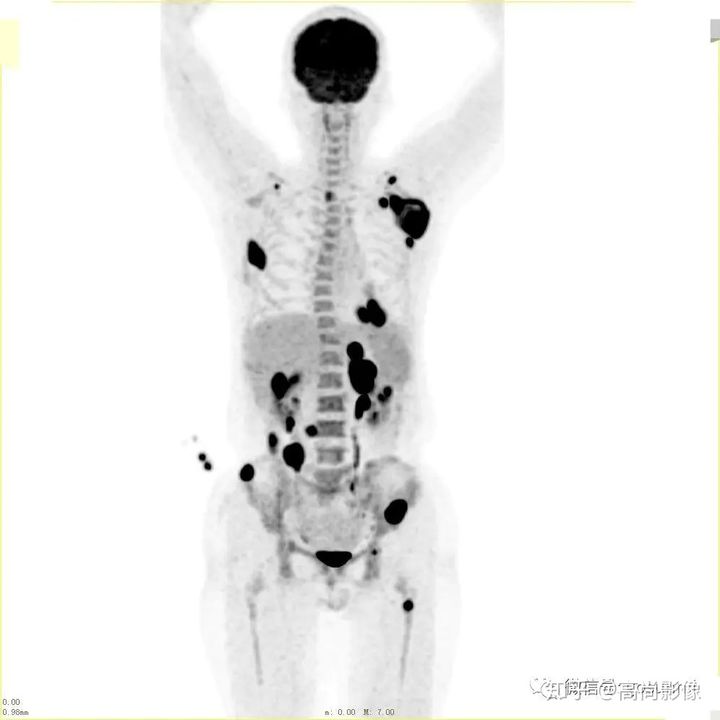

與方大爺有類似病情的一位患者,化療前后的PET/CT影像顯示,腫瘤得到了很好的控制。

肺癌化療前評估的MIP圖

(最大密度投影圖)

肺癌化療后評估的MIP圖

由此可見,惡性腫瘤化療前后的全身PET/CT評估有多重要,尤其對于惡性腫瘤患者來說,時間就是生命,早一天完善診斷,早一天得到正確的治療,預(yù)后就會更佳。